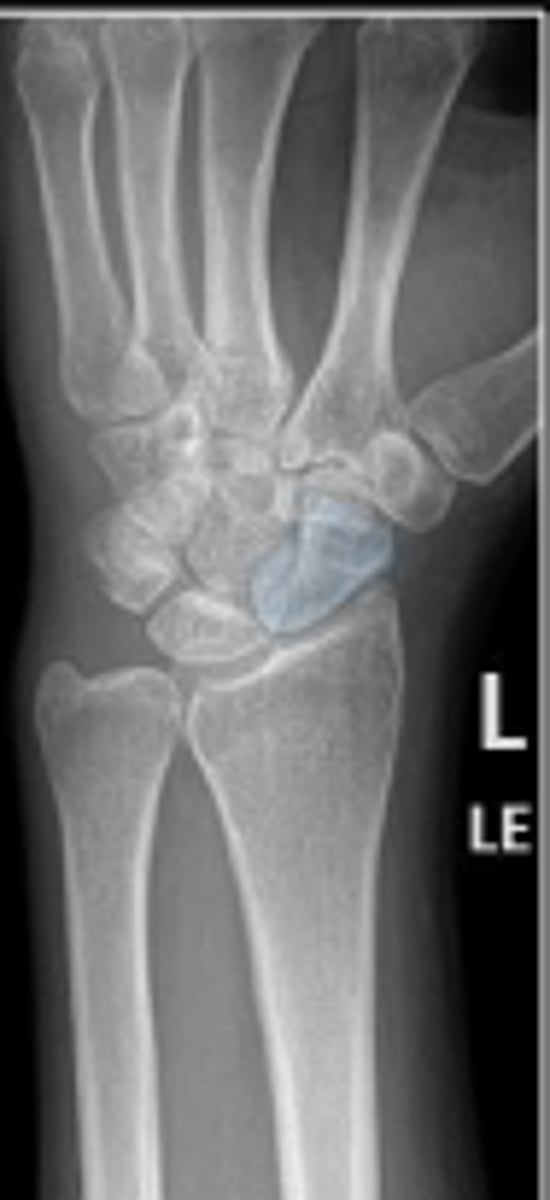

Left lateral wrist

What is the name of the radiographic view?

Left lunate

What is outlined?